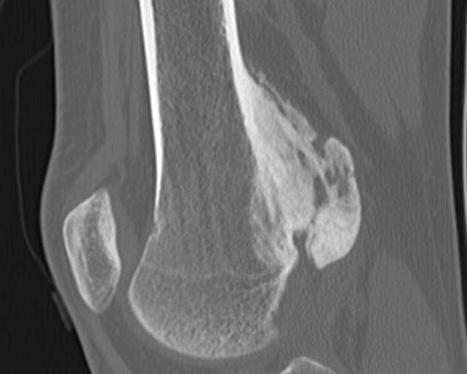

CT

Can be used to differentiate from osteochondroma

1. Parosteal OS

- attached to cortex growing into soft tissue

- normal cortex intact

Parosteal Osteosarcoma proximal tibia